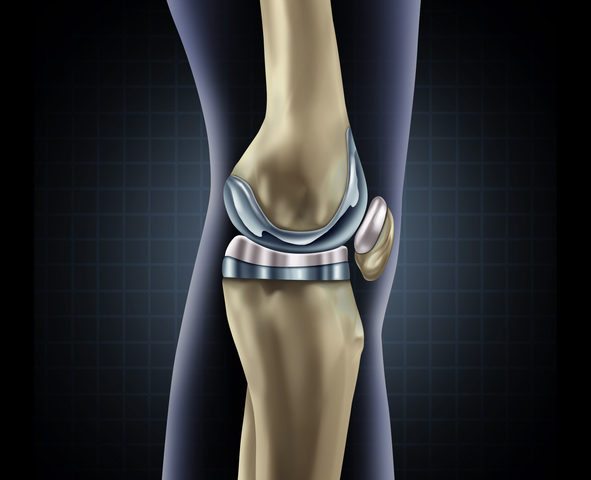

During knee replacement surgery, knee joints damaged by arthritis can be replaced with an artificial knee, also known as a prosthetic knee. A prosthetic knee can help restore mobility and reduce pain in the affected knee. When the joints of both knees are damaged, double knee replacement may be recommended. A doctor will usually recommend…

Knee replacement removes a damaged knee joint and replaces it with an artificial joint. Your knee is the largest joint in your body. It’s involved in most of your movements throughout the day. The goal of knee replacement, also known as knee arthroplasty, is to restore pain-free range of motion and function. When it comes…